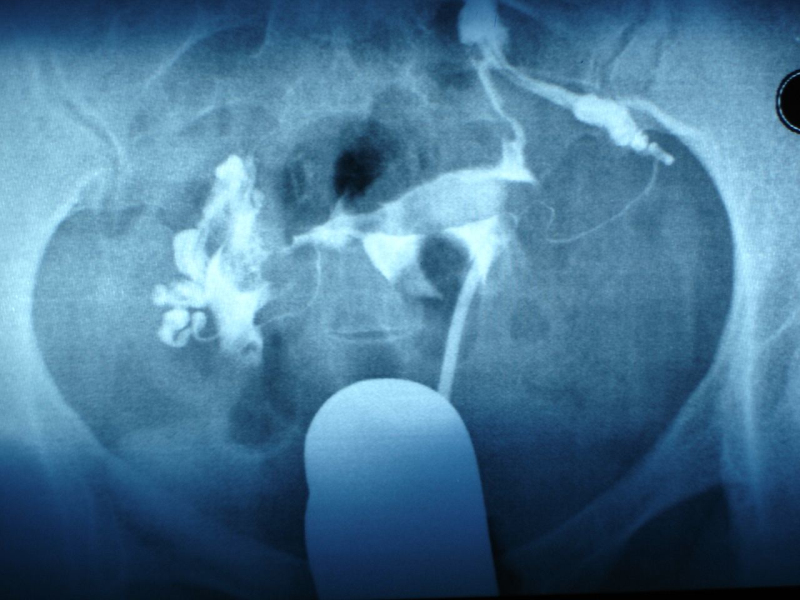

手剥胎盘是什么什么呢?简单点讲,就是孩子正常出生后,胎盘不能自然排出,医生将手伸进子宫里面将粘连在子宫壁上的胎盘用手撕扯下来。是不是听着就疼?

首先,产科大夫会把手从产道中伸进去,伸到子宫中,几乎半只胳膊就进去了,摸到胎盘附着的位置。

然后,产科大夫会用另一只手压住妈妈的肚子,扶好不让胎盘的位置乱动,然后用手指沿着胎盘和子宫附着的位置一点点抠出来。如果顺利的话,整个胎盘能全部取出。

把大块胎盘取出后,接下来,手还要伸进子宫,再去摸一遍,检查子宫壁上是否有胎盘的碎片残留,因为必须要清理的干干净净。